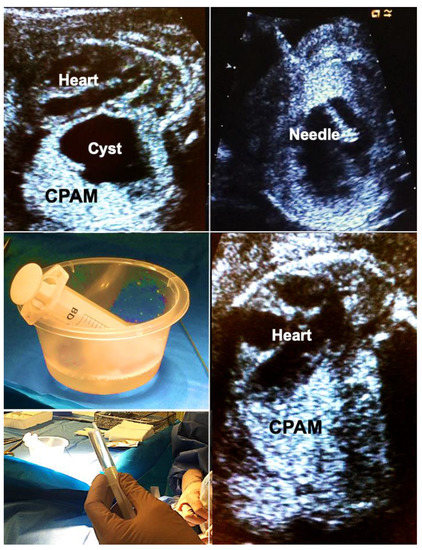

In brief, materno–fetal anesthesia is initiated to guarantee both maternal and fetal immobilization. After surgical cleansing and draping of the maternal abdomen, a 2–3 mm skin incision is made, promptly followed by the insertion of an 18- to 20-gauge trocar needle directed into the largest proximal cyst. Subsequently, the fluid is aspirated from the cyst and its communicating cystic parts until the punctured structure collapses almost entirely. This step is followed by instillation of 5–10 mL of 95% ethanol (BRAUN, Melsungen, Germany) into the cyst system. After 5 min of ablation, the ethanol is withdrawn, and the needle is removed (Figure 5).

Figure 5.

Alcohol ablation in hydropic fetuses with congenital pulmonary airway malformations (CPAM) permits immediate and sustained volume reduction of large, life-threatening malformations. Top left—large left-sided CPAM with contralateral displacement and compression of the fetal heart. Top right—an 18-gauge needle has been placed into a large solitary cyst of the CPAM. Middle left—40 mL of fluid were aspirated from the cyst. Bottom left—then, the cyst is filled with 5 mL of pure ethanol. Bottom right—after 5 min, the ethanol is aspirated. Immediate improvement in cardiac filling can be observed. Hydrops usually resolves within days. In this case, the remainder of gestation remained uneventful. Survival to discharge was achieved after postnatal surgical removal of the CPAM.

Importantly, this approach may also be used to shrink large microcystic lesions which usually are the hardest to treat. In these cases, it is important to consider that the instilled amount of ethanol cannot be withdrawn. Therefore, only very small volumes of 0.1–0.2 mL ethanol have to be used. These must be instilled at multiple locations within the malformation, minimizing the risk of ethanol spillage into the pleural cavity, which could disturb the normal development of the fetal chest wall. This has been the only complication of ethanol ablation we have observed in one of our survivors. Other groups with experience of sclerotherapy with 5% ethanolamine oleate report that its intravascular injection should be avoided because it may result in cardiac necrosis [55,56].